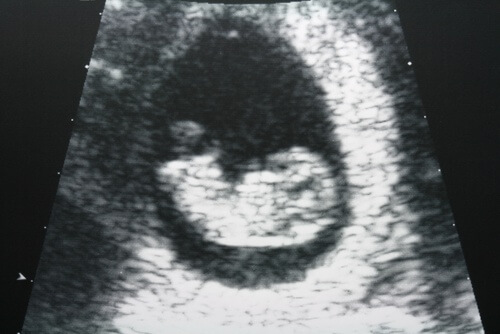

A ultrassonografia é um exame que os médicos costumam pedir frequentemente para analisar possíveis alterações no útero e nos ovários.